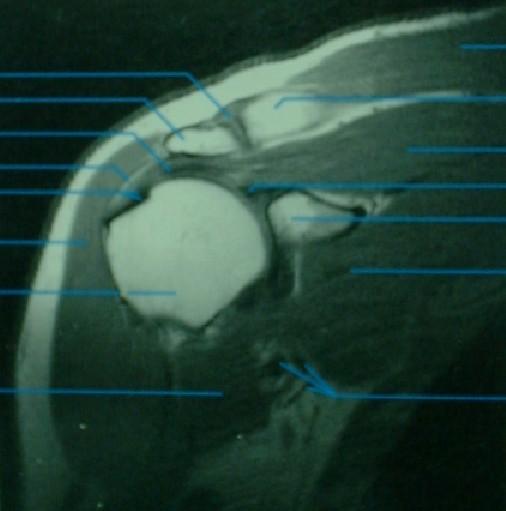

RESONANCIA MAGNETICA

Resonancia magnética

Corte sagital

Corte coronal